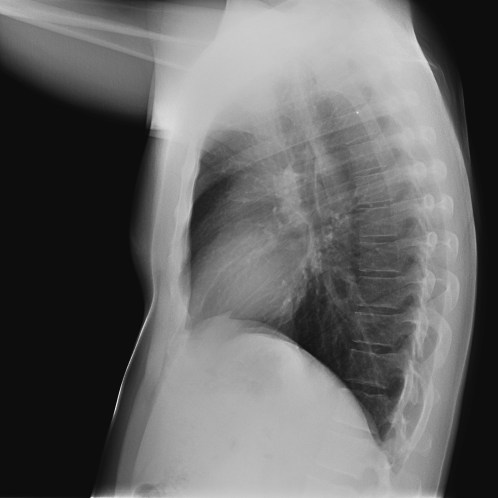

CASO: sospecha de neumonía.

Hallazgos:

- En un principio podríamos decir que existe un aumento de densidad retrocardiaco que podría ser compatible con condensación neumónica a dicho nivel, sin embargo estamos ante una placa poco inspirada, lo cual puede llevarnos a cometer errores diagnósticos.

- Se recomendó volver a realizar la radiografía, observar a continuación:

Ya no se observa el aumento de densidad retrocardiaco, la placa es normal.

INSPIRACIÓN: Una placa bien inspirada es aquella en la que se observar 6-7 arcos costales anteriores o 10-11 arcos costales posteriores. Lo contrario puede producir imágenes falsas de condensaciones o de seudocardiomegalia.